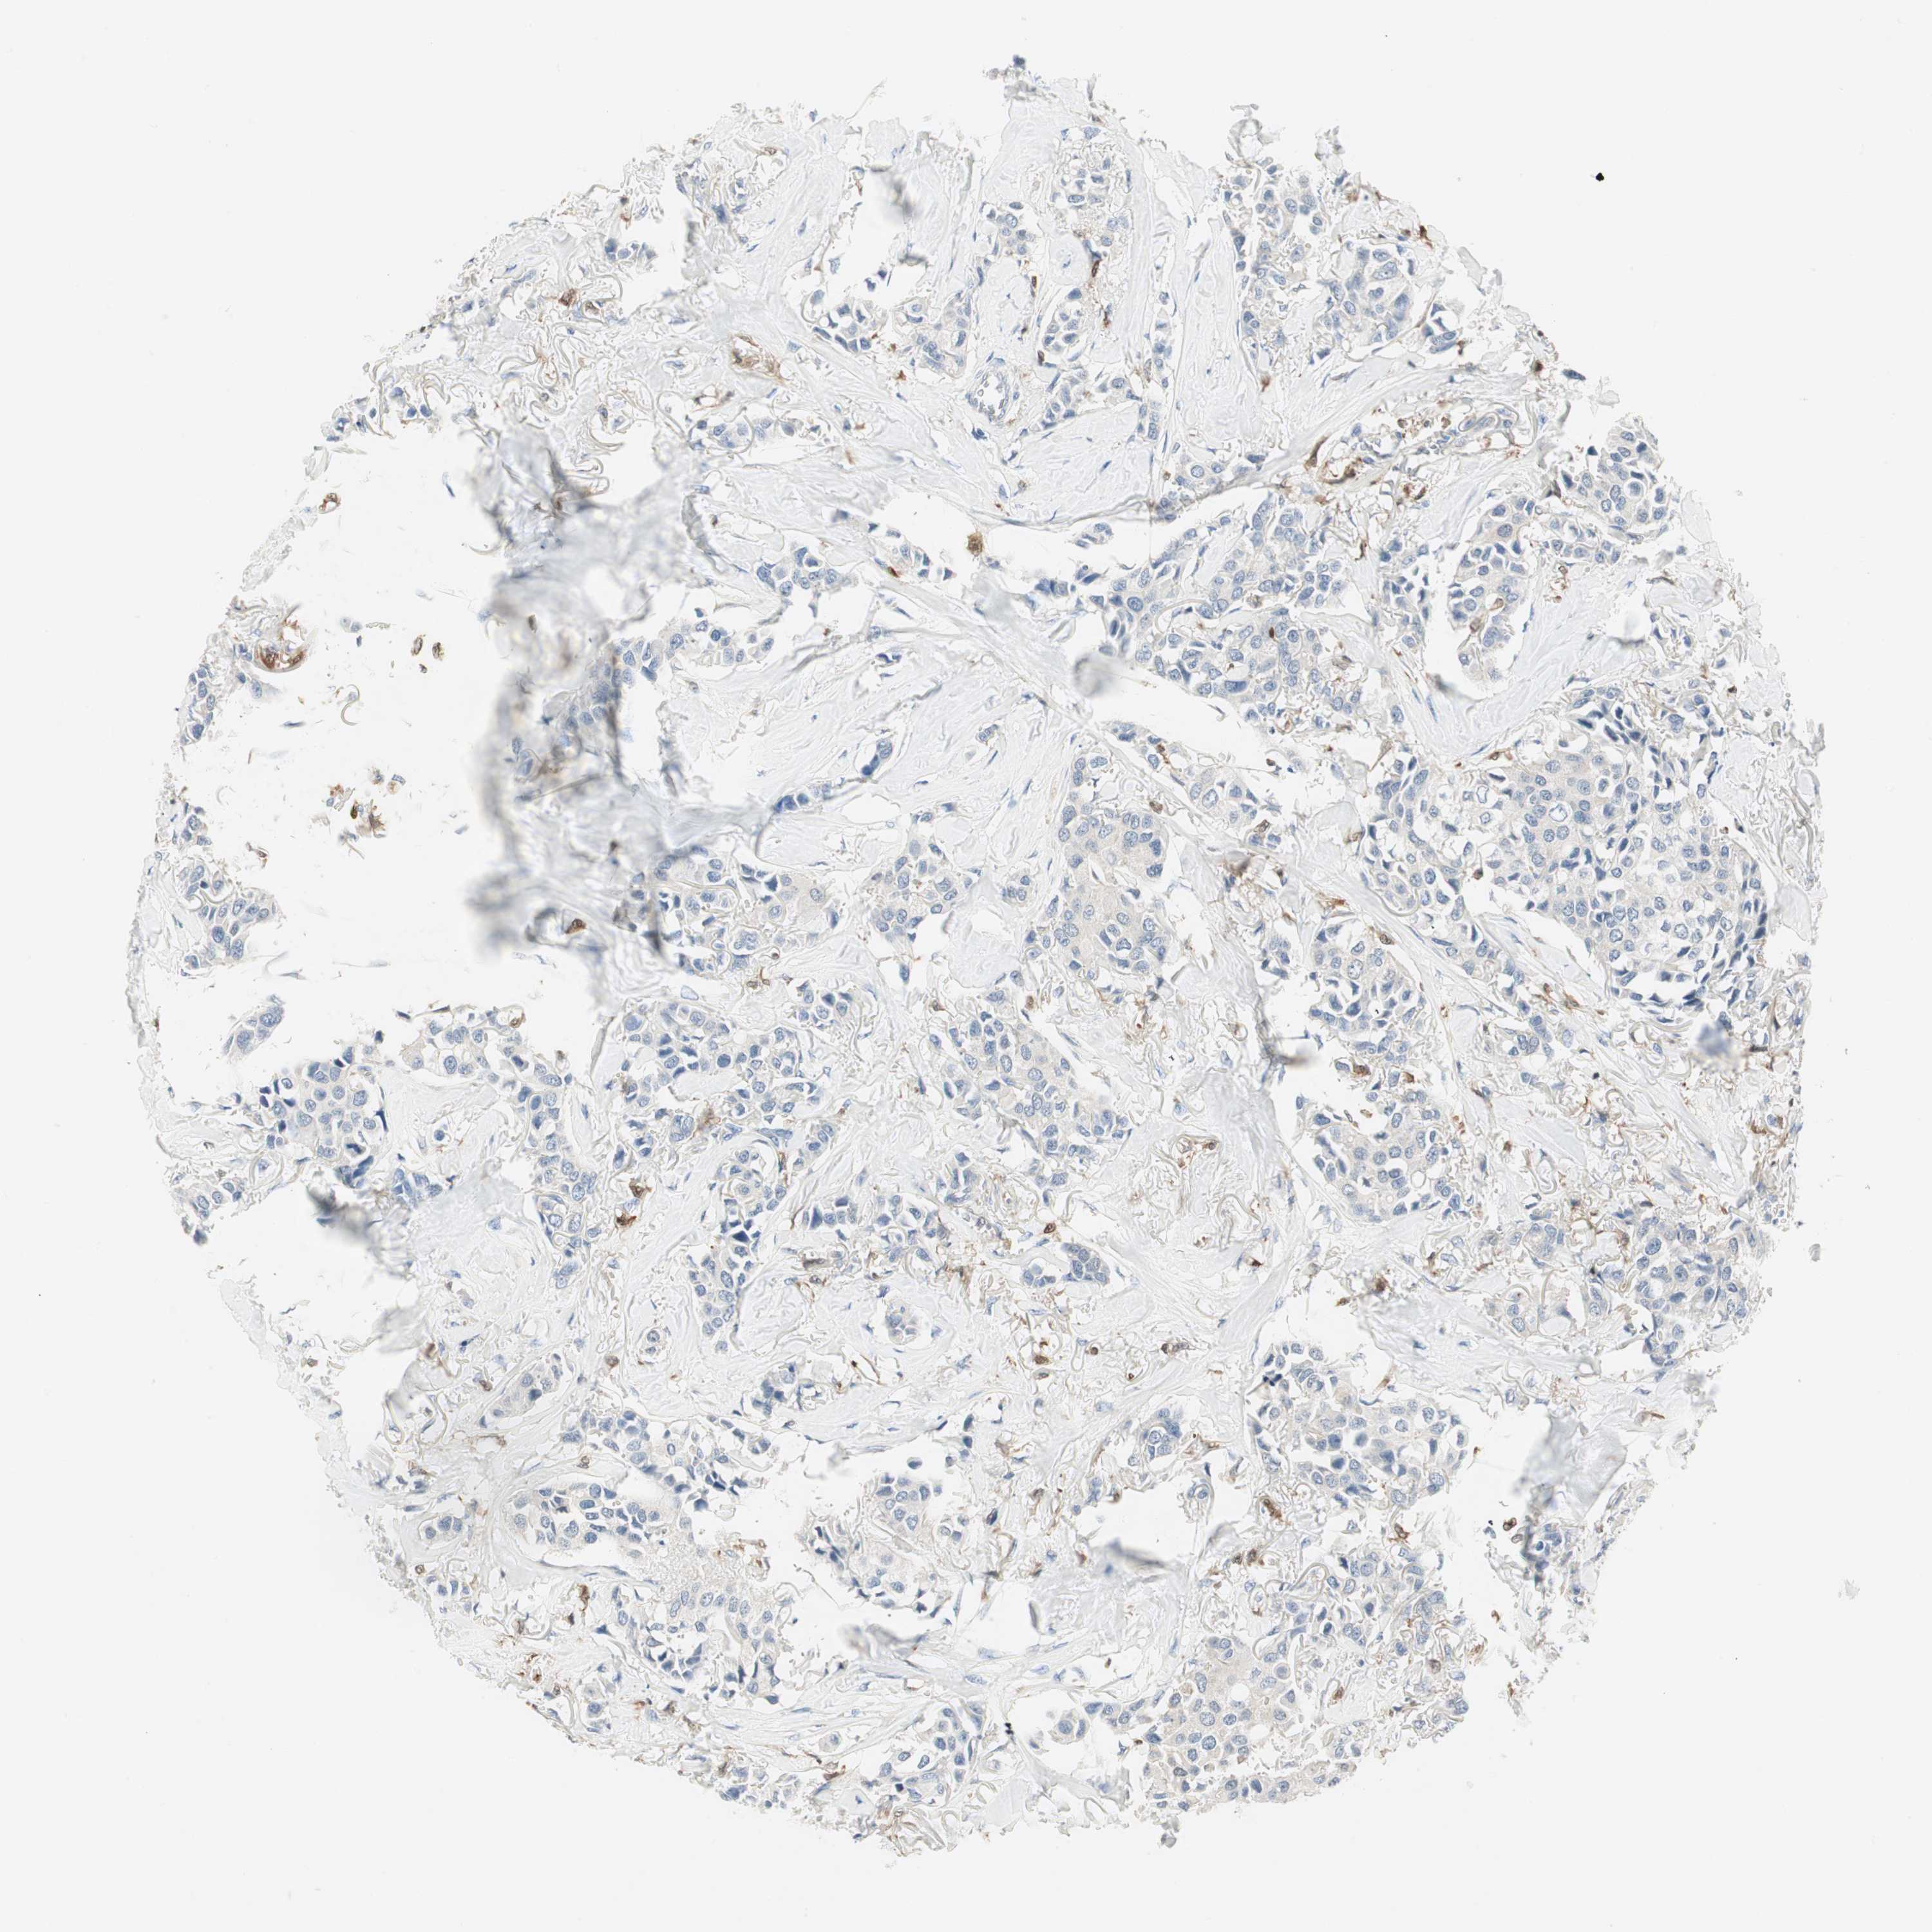

BRCA TCGA BRCA VALIDATION PROTEIN EXPRESSION